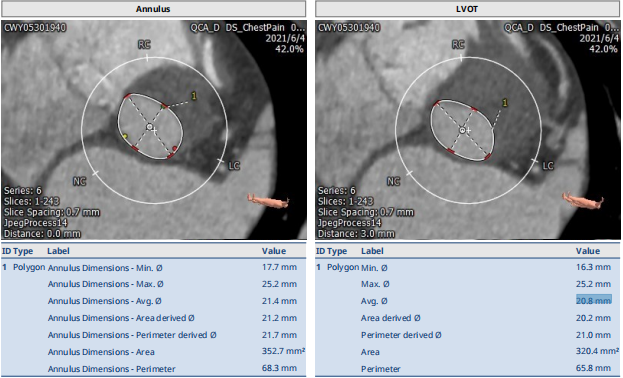

此次手术对象为一名老年女性患者,身高155cm,体重51kg。因“胸闷憋气,咳嗽半年”入院,心超诊断主动脉瓣重度狭窄伴轻度关闭不全,二尖瓣轻度反流,三尖瓣轻-中度反流,肺动脉瓣轻度反流,室间隔心肌肥厚、升主动脉扩张,左室舒张功能降低。既往冠心病20年,平素间断服用“阿司匹林”等药物。术前CT显示患者主动脉瓣口面积352.7 mm²,瓣环平均直径21.4mm,瓣周长68.3 mm;LVOT面积320.4 mm²,平均直径20.8 mm。江磊教授于术后采访中点明了本例TAVR手术操作棘手之处。江教授指出,从术前影像学来看,病人为三叶瓣,这是其一;此次手术最主要的难点则在于病人的左冠较低,而TAVR手术中对于冠脉的最低要求应在瓣环上1公分左右,此例手术患者又恰好处于友好临界值上0.9cm。因此,为规避冠脉阻塞风险,江磊教授团队决定采用SAPIEN 3球扩式瓣膜。“如果使用自膨式瓣膜,冠脉阻塞风险相对来说高一些,而SAPIEN 3是一款球扩式瓣膜,可以最大程度的避免左冠闭塞的风险,同时考虑到患者家庭诉求,我们在综合考量下选择SAPIEN 3瓣膜,事实也证明它的确能发挥这样的效用。”